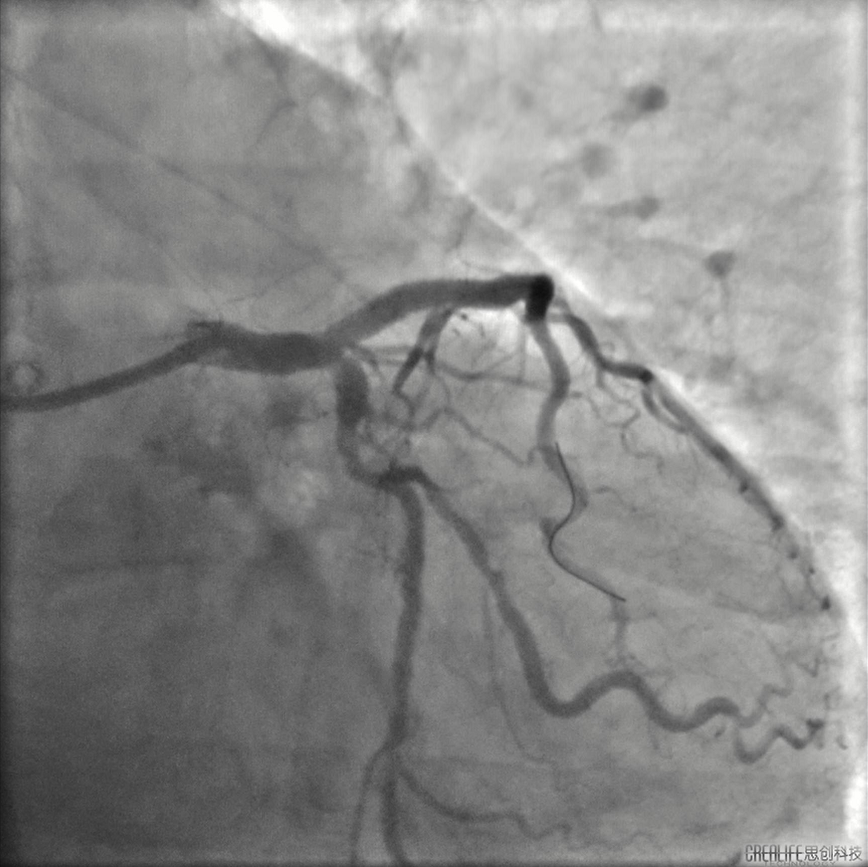

患者男,64岁,2022年6月5日急性下壁心肌梗死行介入干预,于右冠植入支架一枚,6月15日对左冠病变进行治疗。冠脉系统呈右侧优势型,右冠中段支架通畅。左主干大致正常,前降支近端至中段重度狭窄伴明显钙化。对前降支进行介入干预,以2.5*15mm球囊预扩张后,在前降支中段植入2.5*18mm Resolute支架,之后尝试在前降支近端植入 3.0*26mm支架不成功,经反复预扩张后,支架仍无法通过病变,血管内超声证实前降支近端可见环形钙化并重度狭窄。